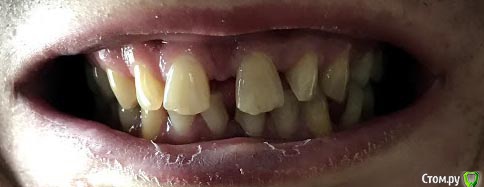

Arkasha18 Опубликовано 4 мая, 2019 Поделиться Опубликовано 4 мая, 2019 (изменено) 35 лет, мужчина.разъезжаются передние зубы все больше и больше, хочу выравнять, насколько ходил по специалистам, все советуют только брекеты.Но остается очень много вопросов по выбору специалиста, т.к. сейчас стоматологов очень много, я не могу выбрать хорошего специалиста, т.к. не разбираюсь в этом. Текущие специалисты меня не устраивают, т.к. допустили уже ряд ошибок которых не должно было быть. Прошу помощи как выбрать специалиста, какие вопросы ему задавать что бы понимать что он специалист хорошо разбирающийся, а не без опытный какой то.набросайте несколько вопросов какие можно задавать пожалуйста. - на например связанные с какими то технологиями, - процессом техническим - варианты брекет систем чем отличаются может что то спросить в общем не знаю..хочется задать вопросы и что бы было понятно кто передо мной, ленивый, знающий, или нет и т.п. если кто то посоветует в питере специалиста на севере города (коменда, старая деревня, пионерская) буду безмерно благодарен И второй вопрос у меня три импланта, верхний на коронке, нижние два без. соот-но придется их снимать? снимки прикрипляю Изменено 4 мая, 2019 пользователем Arkasha18 Ссылка на комментарий